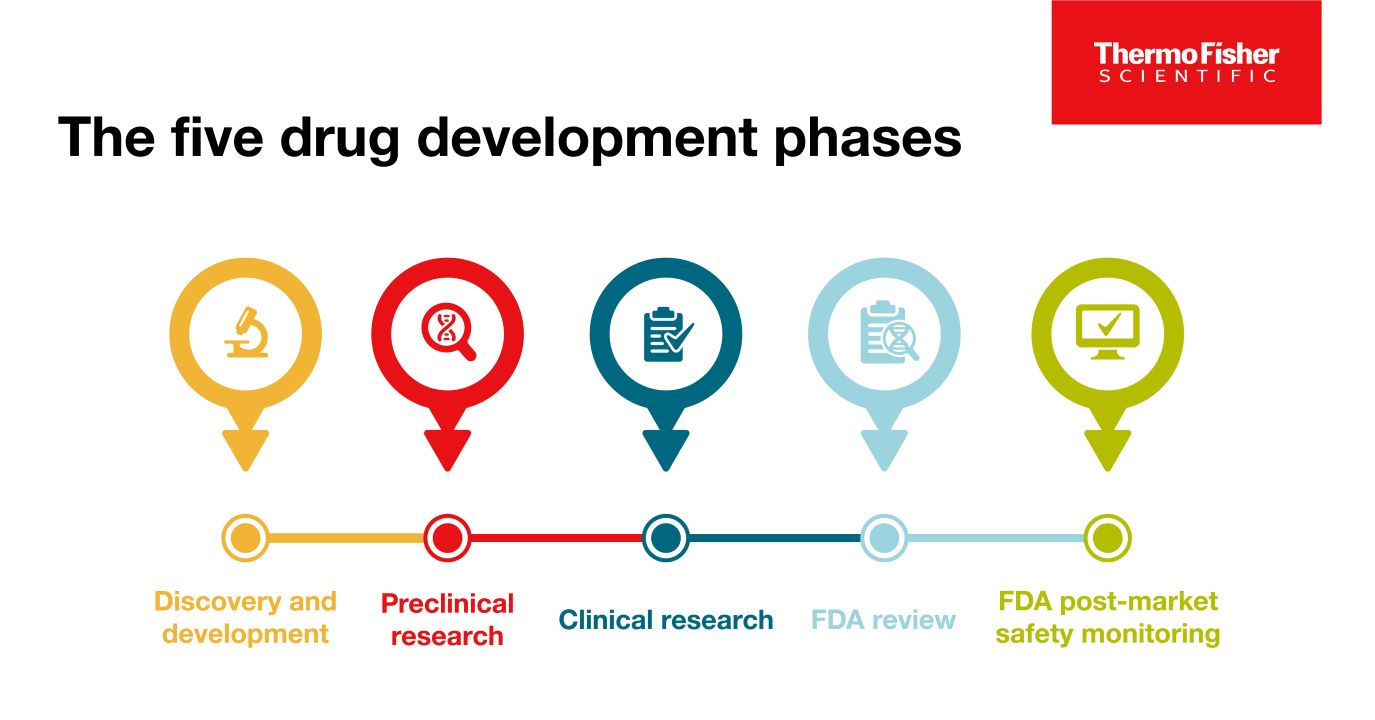

Blog

The 5 drug development phases

To be deemed a “success,” a new drug must make it through five specific phases: 1) discovery and development, 2) preclinical research, 3) clinical research, 4) FDA review, and 5) safety monitoring.

Read Blog